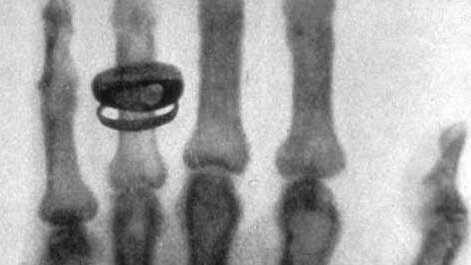

Вильгельм Конрад Рентген совершил великое открытие и подарил человечеству удивительные Х-лучи. Событие кардинально изменило медицинский мир: сейчас врачи могут заглянуть внутрь пациентов помимо метода внешнего осмотра. Следовательно, появилась возможность диагностировать различные заболевания с помощью рентгеновских лучей. Одной из сфер применения такой методики стала стоматология. Южнокорейская компания Ватек производит уникальное рентген-оборудование с инновационным программным обеспечением. Первоначальным истоком уникальных разработок и стало обнаружение Рентгеном лучей...